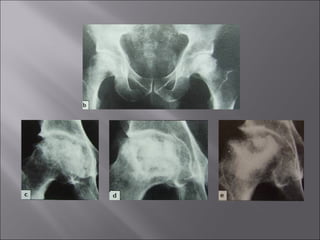

 Circumscribed bone

necrosis

 CausesCauses

 Interruption of the arterial

blood flow

 Slowing of the venous

outflow leading to

inadequate perfusion

 Common siteCommon site ::

 Femoral headFemoral head

 Femoral condyls

 Humeral head

 Capitulum of humerus

 ScaphoidScaphoid (proximal part)

 TalusTalus (body)

 Lunate

 Clinical featuresClinical features

 Joint pain, stiffness, swelling

 Restricted movement

 X-RayX-Ray

 ↑ bone density

 Subarticular fracturing

 Bone deformity

 TreatmentTreatment

 Avoid weight bearing on the necrotic bone

 Revascularisation (using vascularised bone grafts)

 Excision of the avascular segment

 Replacement by prostheses